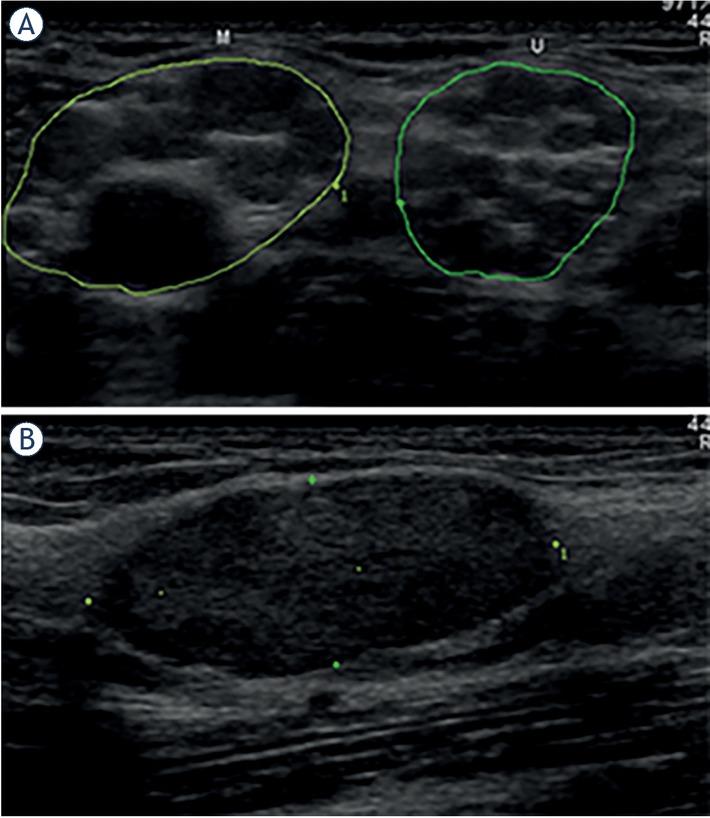

We could divide our patient cohort into several groups. The first group consisted of 4 patients with numerous PNTs in several peripheral nerves. Two of patients from this group with numerous neurofibromas had known NF1 and a single patient with schwannomas had NF2. Diagnosis in a remaining patient (#13), with numerous neurofibromas in all US examined peripheral nerves (Figure 1), has not been established yet.

(A) Transverse ultrasonographic (US) view of the median (M) and ulnar (U) nerve in the axillary region showing numerous globular hypoechoic peripheral nerve tumours (PNTs) causing largely increased nerve cross sectional areas (CSAs, 148 mm2 and 101 mm2, respectively). (B) Longitudinal view of a single partially encapsulated, slightly lobulated and rather homogenous oval PNT (length 24 mm, thickness 9 mm) with central, but poorly defined nerve-tumour transition.5 Most probably these numerous PNTs are neurofibromas, although diagnosis in this 52-year-old woman presenting with peripheral neuropathy, primary lymphedema, and history of mitral and aortic valve surgery (patient #13, Tables 2–3), is not known yet.